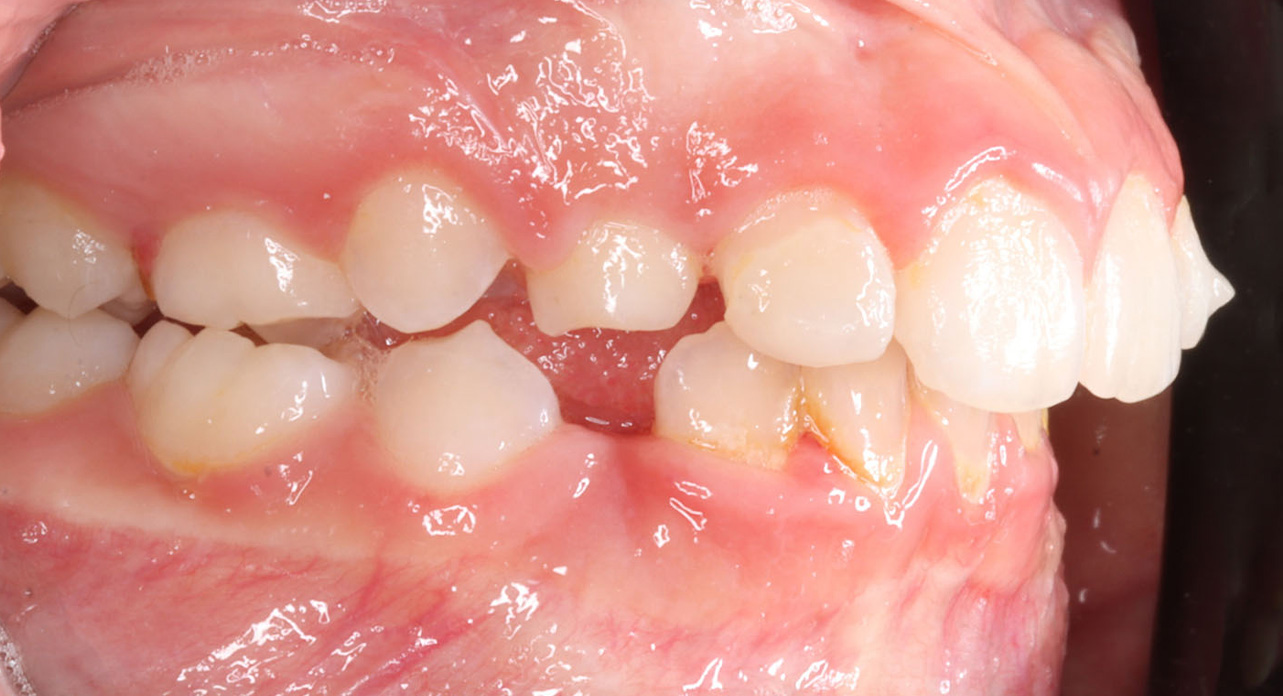

Case report of a 9-year-old female patient in the intermediate phase of mixed dentition. The patient presents with moderate upper and lower crowding, narrow arches, Class II molar relationship on the right side, premature loss of tooth 83, deviation of the lower midline to the right, deep bite, and a crossbite on the right side affecting only the deciduous dentition.

The goal of the treatment was to achieve transverse development of both arches, proclination of upper and lower incisors to correct the deep bite, and to create space for the blocked tooth.